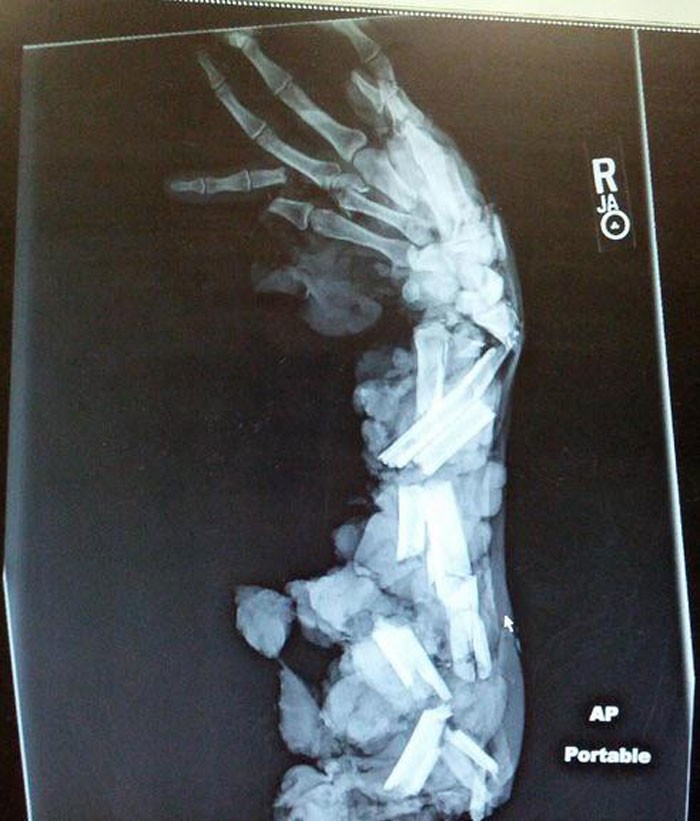

6. Рентгеновский снимок руки, попавшей в мясорубку